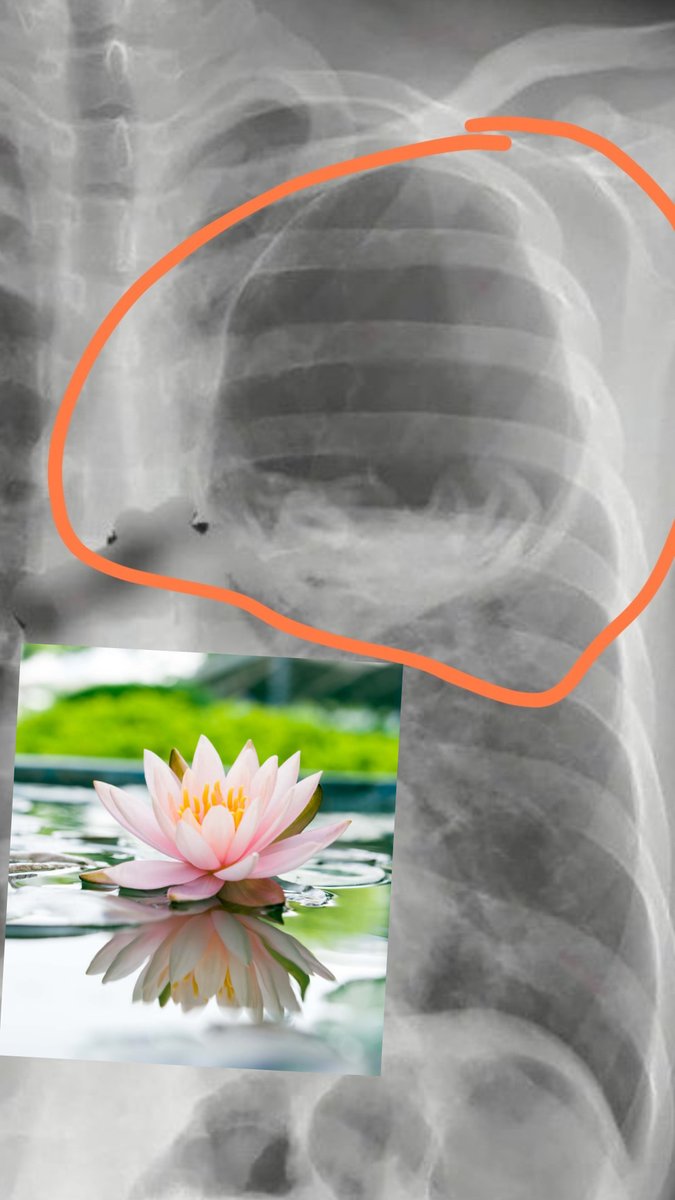

Water Lily sign

يميز ال echinococcosis عندما ينفجر الكيس و تبقى أغشية الكيس تطيش في داخله !